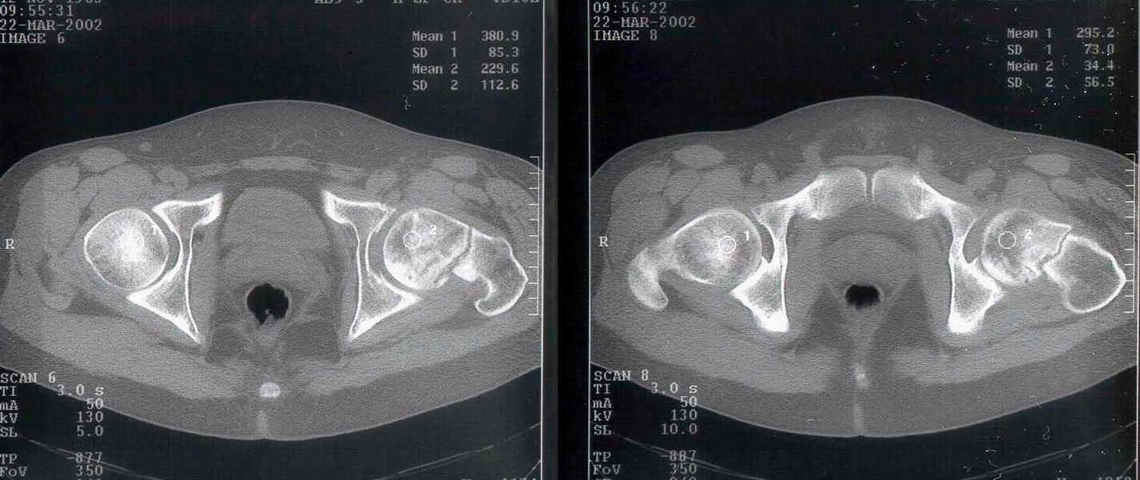

Alexander Chelnokov 02 Апрель 2002, 14:56

Вчера сделали остеотомию, делали близко к тому, как на той картинке.

Картинка тут.

То, что получилось, в приложении (без такой красивой анимации, к сожалению